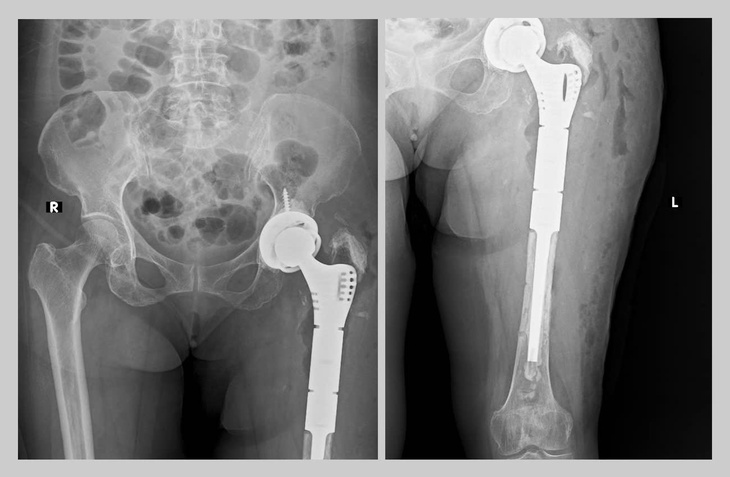

Các bác sĩ ở Huế tái tạo khớp háng và hơn nửa xương đùi cho nữ bệnh nhân 71 tuổi – Ảnh: THƯỢNG HIỂN

Ngày 24-6, Bệnh viện Trung ương Huế cho biết vừa phẫu thuật thành công ca thay lại khớp háng và hơn nửa xương đùi bằng Megaprosthesis (kỹ thuật thay khớp nhân tạo chuyên sâu) lần đầu tiên được triển khai ở khu vực miền Trung – Tây Nguyên.

Bệnh nhân là bà P.T.X. (71 tuổi, ngụ phường An Cựu, quận Thuận Hóa, TP Huế), từng thay khớp háng nhân tạo 17 năm trước, và phẫu thuật lại do lỏng khớp vào năm ngoái.

Qua thăm khám, các bác sĩ phát hiện bà bị tiêu xương lan rộng, gãy quanh khớp háng cũ, gãy cả vật liệu kết hợp xương, trục chân lệch và bị rút ngắn hơn 7cm – tổn thương nặng, có nguy cơ mất chức năng vận động nếu không được xử lý kịp thời.

Bệnh nhân được chỉ định thay lại toàn bộ khớp háng và hơn nửa xương đùi bằng mô cấy kim loại đặc biệt Megaprosthesis.

Ca mổ kéo dài gần 4 giờ, do TS.BS Nguyễn Nguyễn Thái Bảo – trưởng khoa phẫu thuật khớp – y học thể thao của bệnh viện – trực tiếp thực hiện cùng ê kíp chuyên môn.

Megaprosthesis là giải pháp điều trị hiệu quả trong các trường hợp gãy xương diện rộng, biến chứng sau thay khớp hay tổn thương do ung thư xương, vốn trước đây thường phải cắt cụt chi.